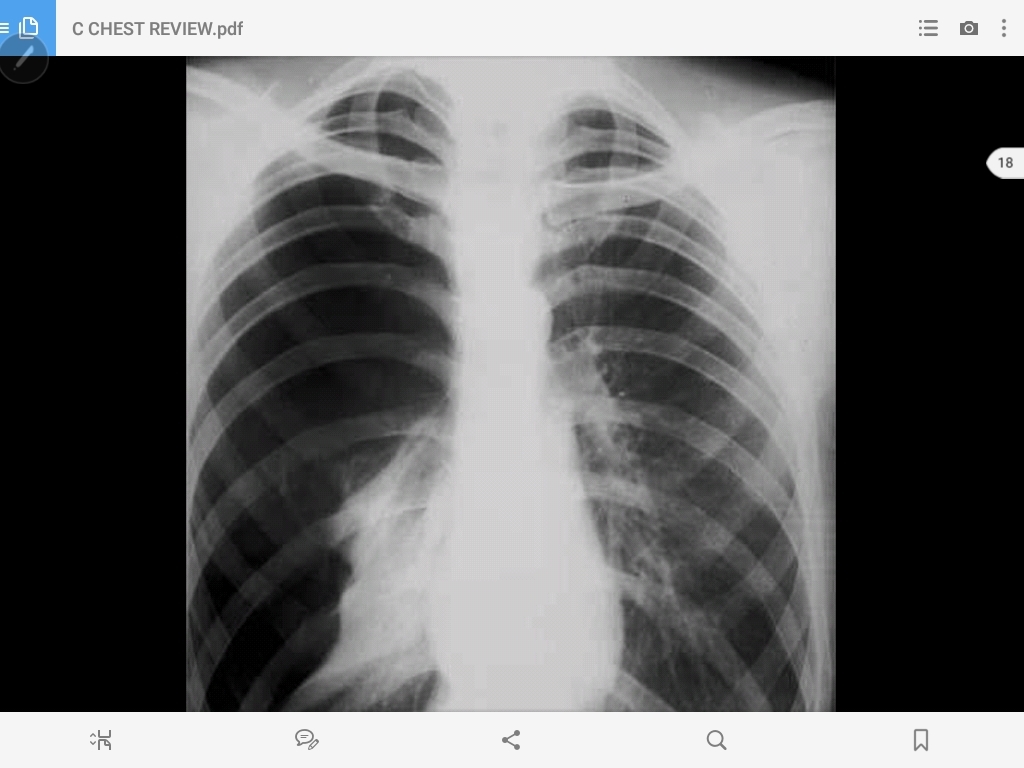

atalectasis of the left lung